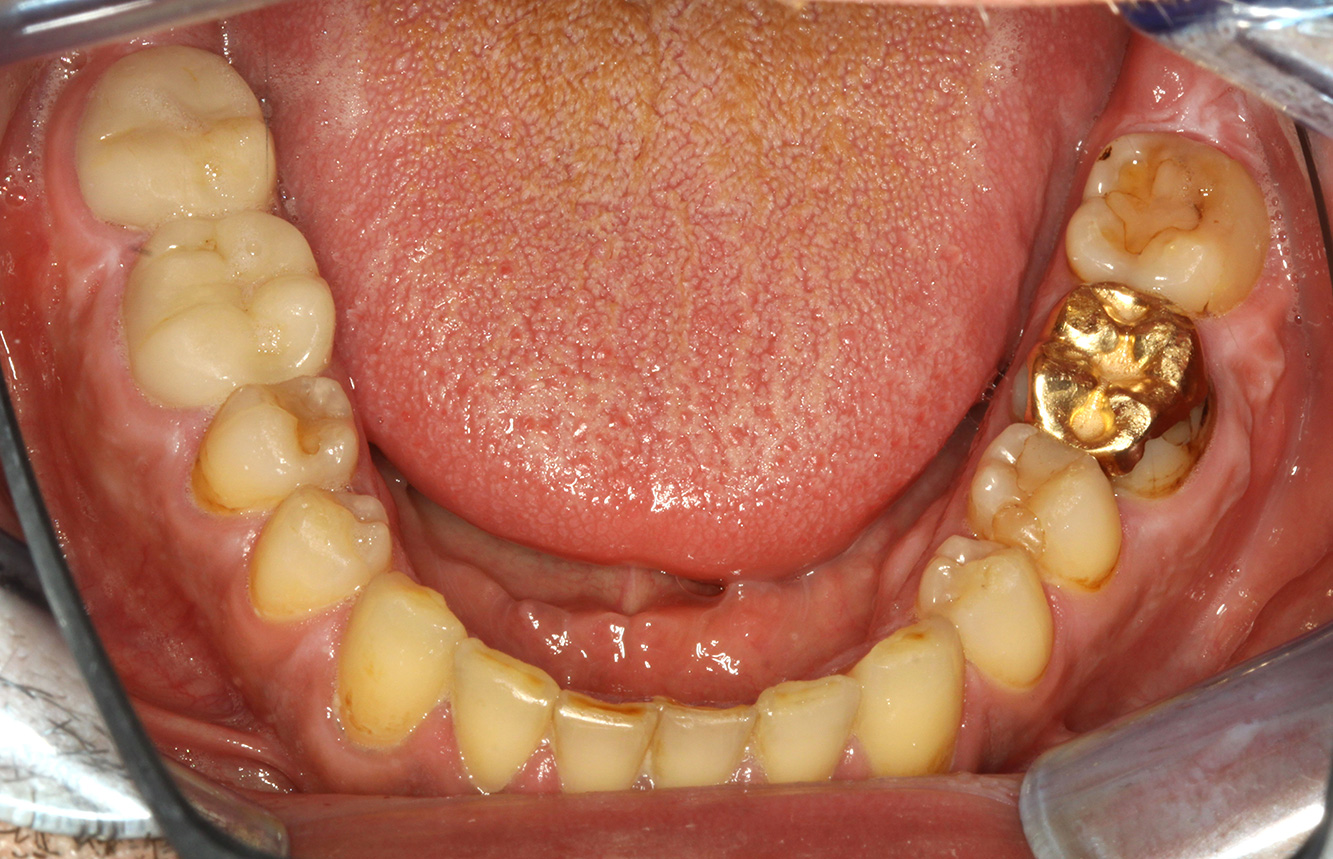

Pacient sănătos cu boală parodontală incipientă

Pacientul în vârstă de 68 de ani nu are nicio afecțiune generală și nu ia niciun medicament care ar putea fi relevant pentru sănătatea sa orală, iar stilul său de viață nu prezintă niciun risc special. Pacientul are două implanturi dentare (cadranul 3, de cinci ani) și un caz anterior de boală parodontală (stadiul IV, gradul B) cu pierderea dinților. În prezent, condițiile parodontale sunt stabile. Cu toate acestea, parodontoza crește semnificativ complicațiile biologice ale implanturilor și există riscul de pierdere a implanturilor (21). Se pot determina patru recomandări pentru ședința de profilaxie. mai multe